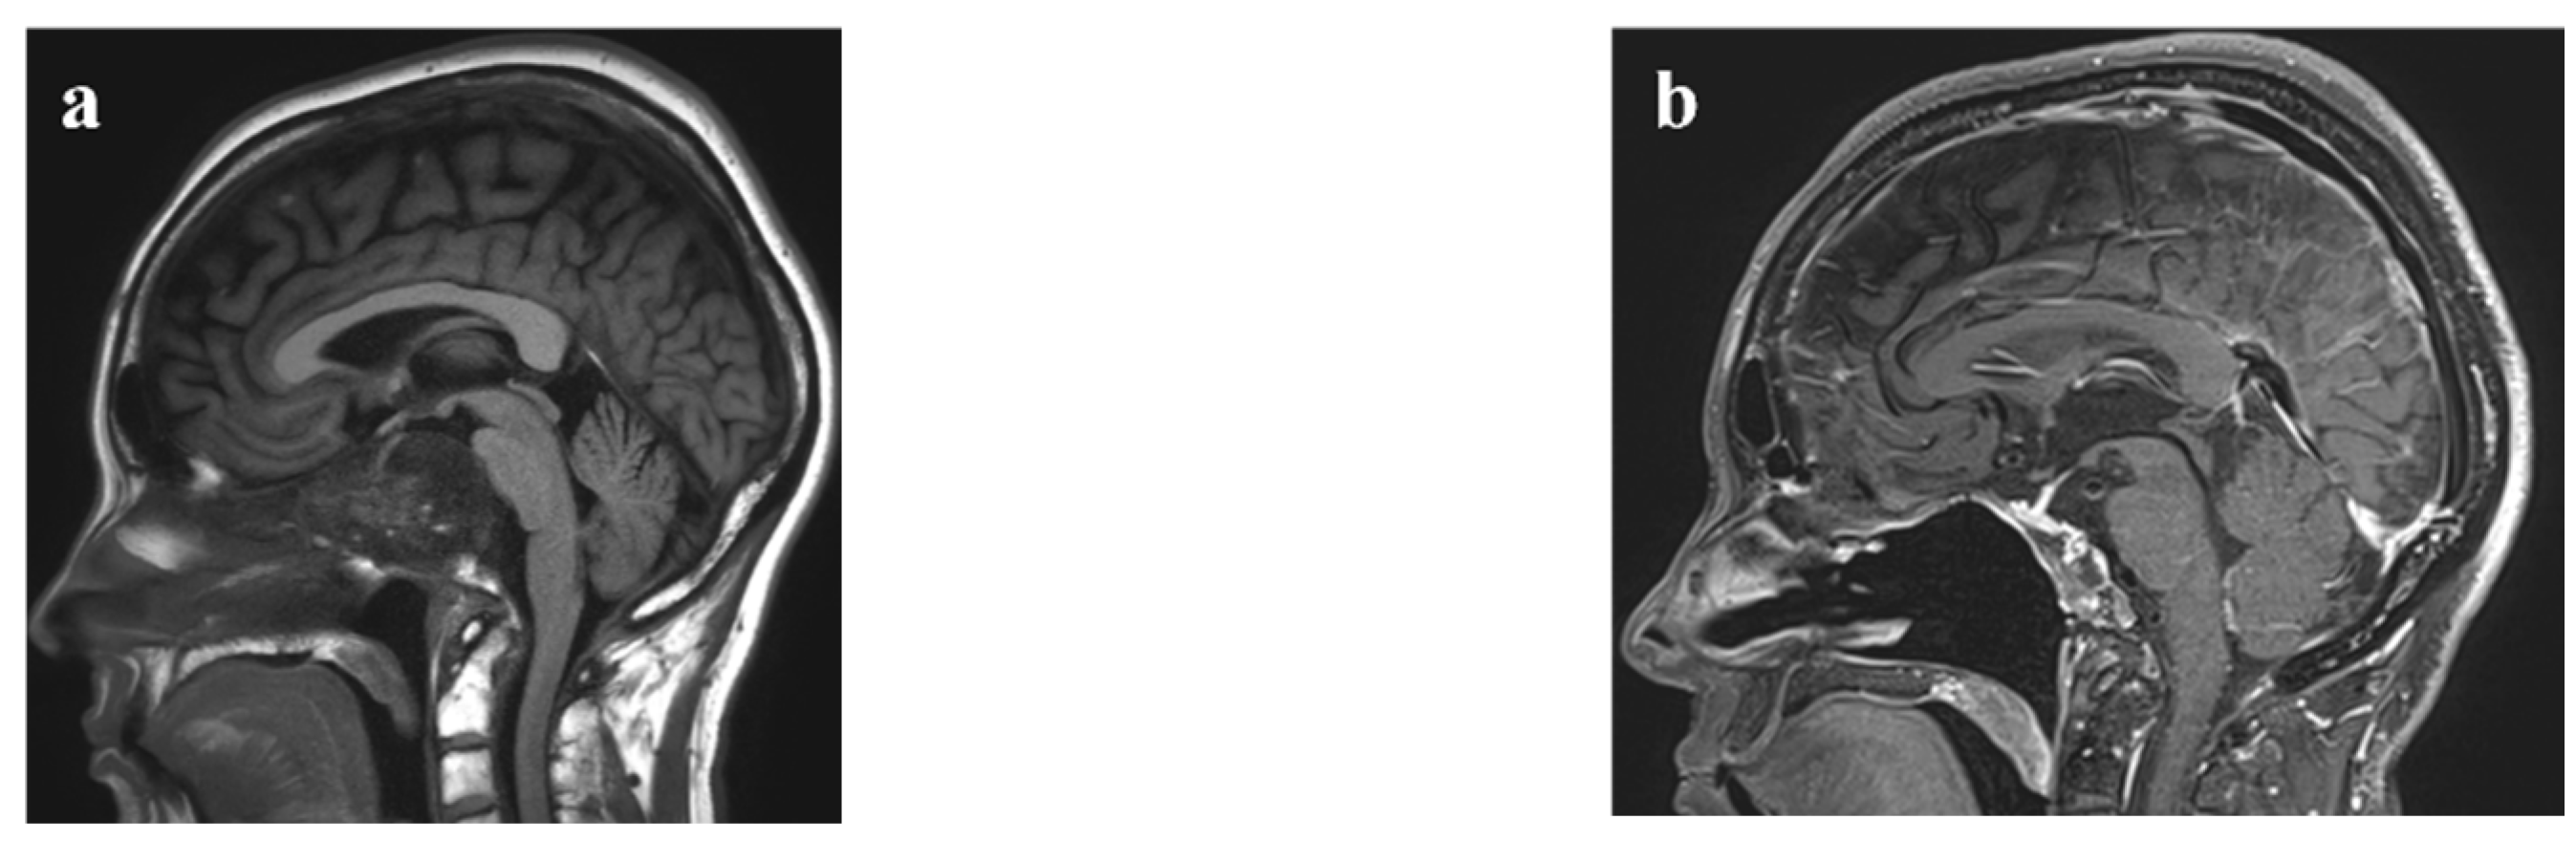

| Operative approach | 36 | - | ||

| EEA | 1 | 6 (32%) | 30 (77%) | |

| Endoscopic transcervical | 4 | 0 | 1 | |

| MicroEA | 10 | 4 | 0 | |

| Open craniotomy | 2 | 7 | 3 | |

| EEA, open craniotomy | 2 | 0 | 2 | |

| EEA, OC fusion | 12 | 0 | 2 | |

| EEA, OC fusion, endoscopic transcervical | 0 | 1 | ||

| Midline mandibular osteotomy | 2 | 0 | ||

| Degree of resection | 0.002 | |||

| GTR or NTR | 28 | 3 (16%) | 25 (64%) | |

| STR | 30 | 16 | 14 | |